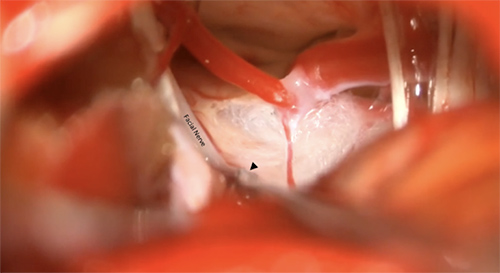

Facial nerve massage is performed under general anesthesia with the patient placed in the lateral decubitus position. During the procedure, Dr. Sekula accesses the cerebellopontine angle using retrosigmoid craniectomy measuring roughly 2 × 1.5 cm. The facial nerve is inspected from its root exit point at the brainstem to the porus acousticus for neurovascular compression. After confirming the absence of neurovascular compression, Dr. Sekula uses a micro dissector to gently rub or massage the facial nerve along the attached segment and the distal cisternal segment of the nerve for <10 seconds in each location. Before and after the facial nerve is massaged, the nerve is probed with monopolar stimulation. Notably, the fascicles of the facial nerve are not separated from each other. The wound is then closed in layers.

Facial nerve massage for treatment of hemifacial spasm refractory to MVD; arrowhead points to the dissector used to massage the facial nerve.